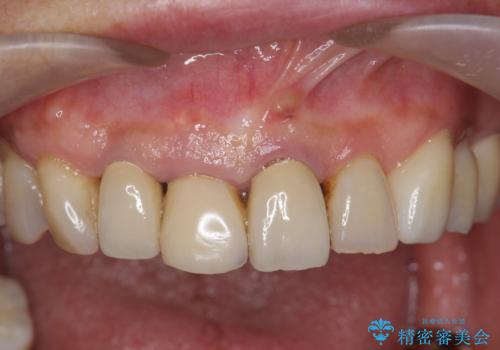

2.

2. ぐらつく前歯 ブリッジ治療の治療中